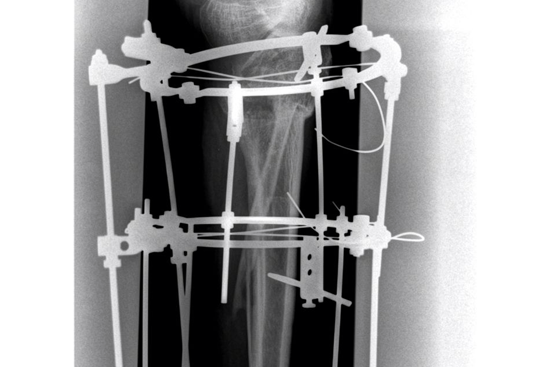

HTO Ilizarov